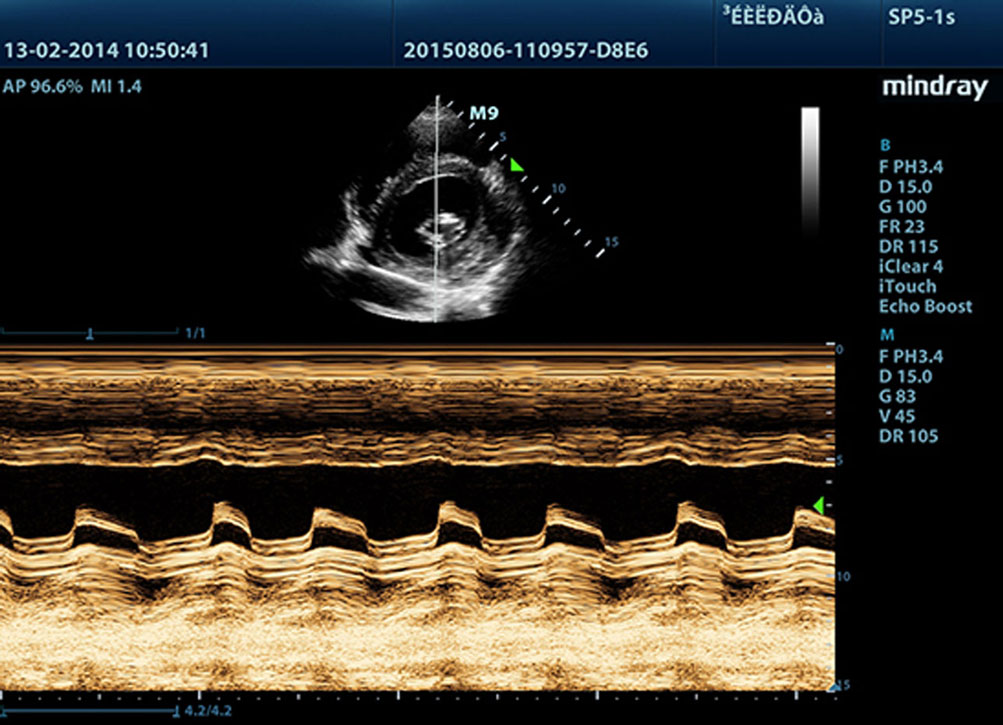

3T Transducer Technology with Single Crystal

Providing sharper images, all probes compatible with the M9 come equipped with MindrayŌĆÖs unique 3T transducer technology. Enhanced with the addition of single crystal technology, M9 offers better penetration and color dynamic flow, especially during difficult-patient scanning.

Echo Boost?

MindrayŌĆÖs unique adaptive signal processing technology with intelligent echo detection, designed to utilize the native signal-to-noise information to enhance the weak echo signals while suppressing the surrounding clutter noise, providing more balanced image brightness and improved visualization of myocardium tissue layers.